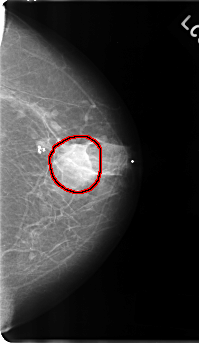

C_0177_1.LEFT_CC

FILE: C_0177_1.LEFT_CC.OVERLAY

TOTAL_ABNORMALITIES 1

ABNORMALITY 1

LESION_TYPE MASS SHAPE IRREGULAR MARGINS ILL_DEFINED

ASSESSMENT 4

SUBTLETY 3

PATHOLOGY MALIGNANT

TOTAL_OUTLINES 1

BOUNDARY